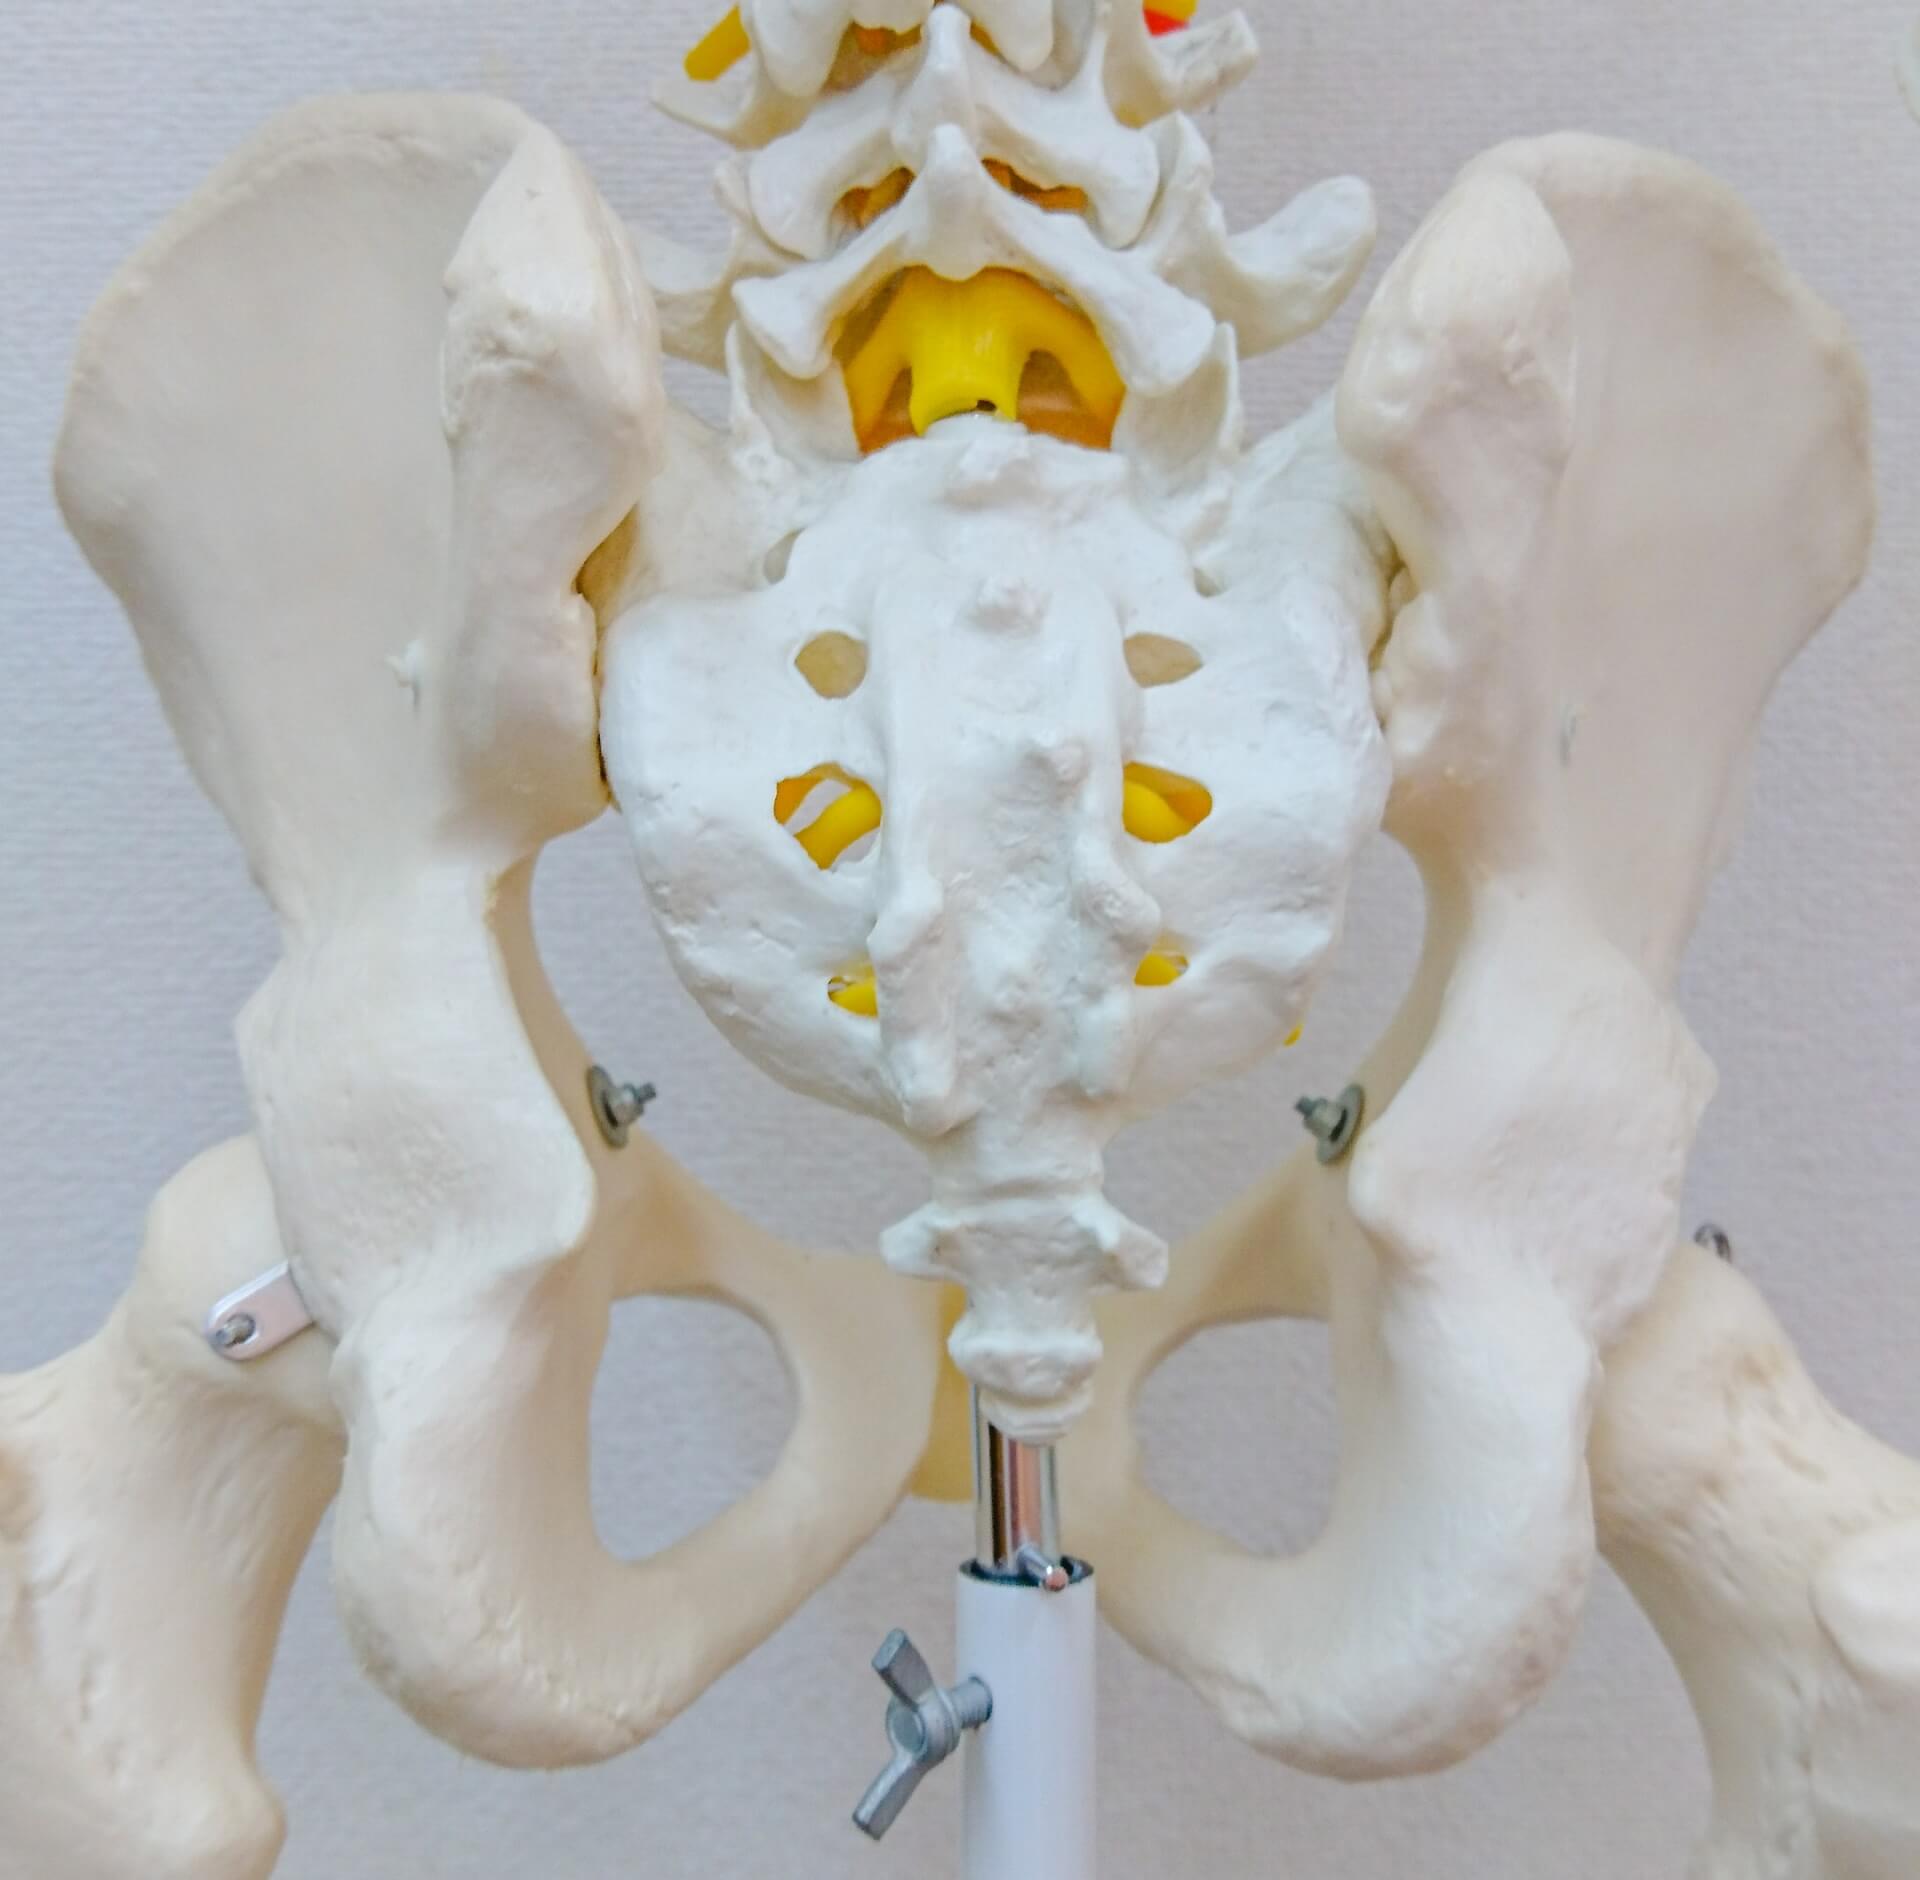

人工股関節には4つのインプラントがあります。